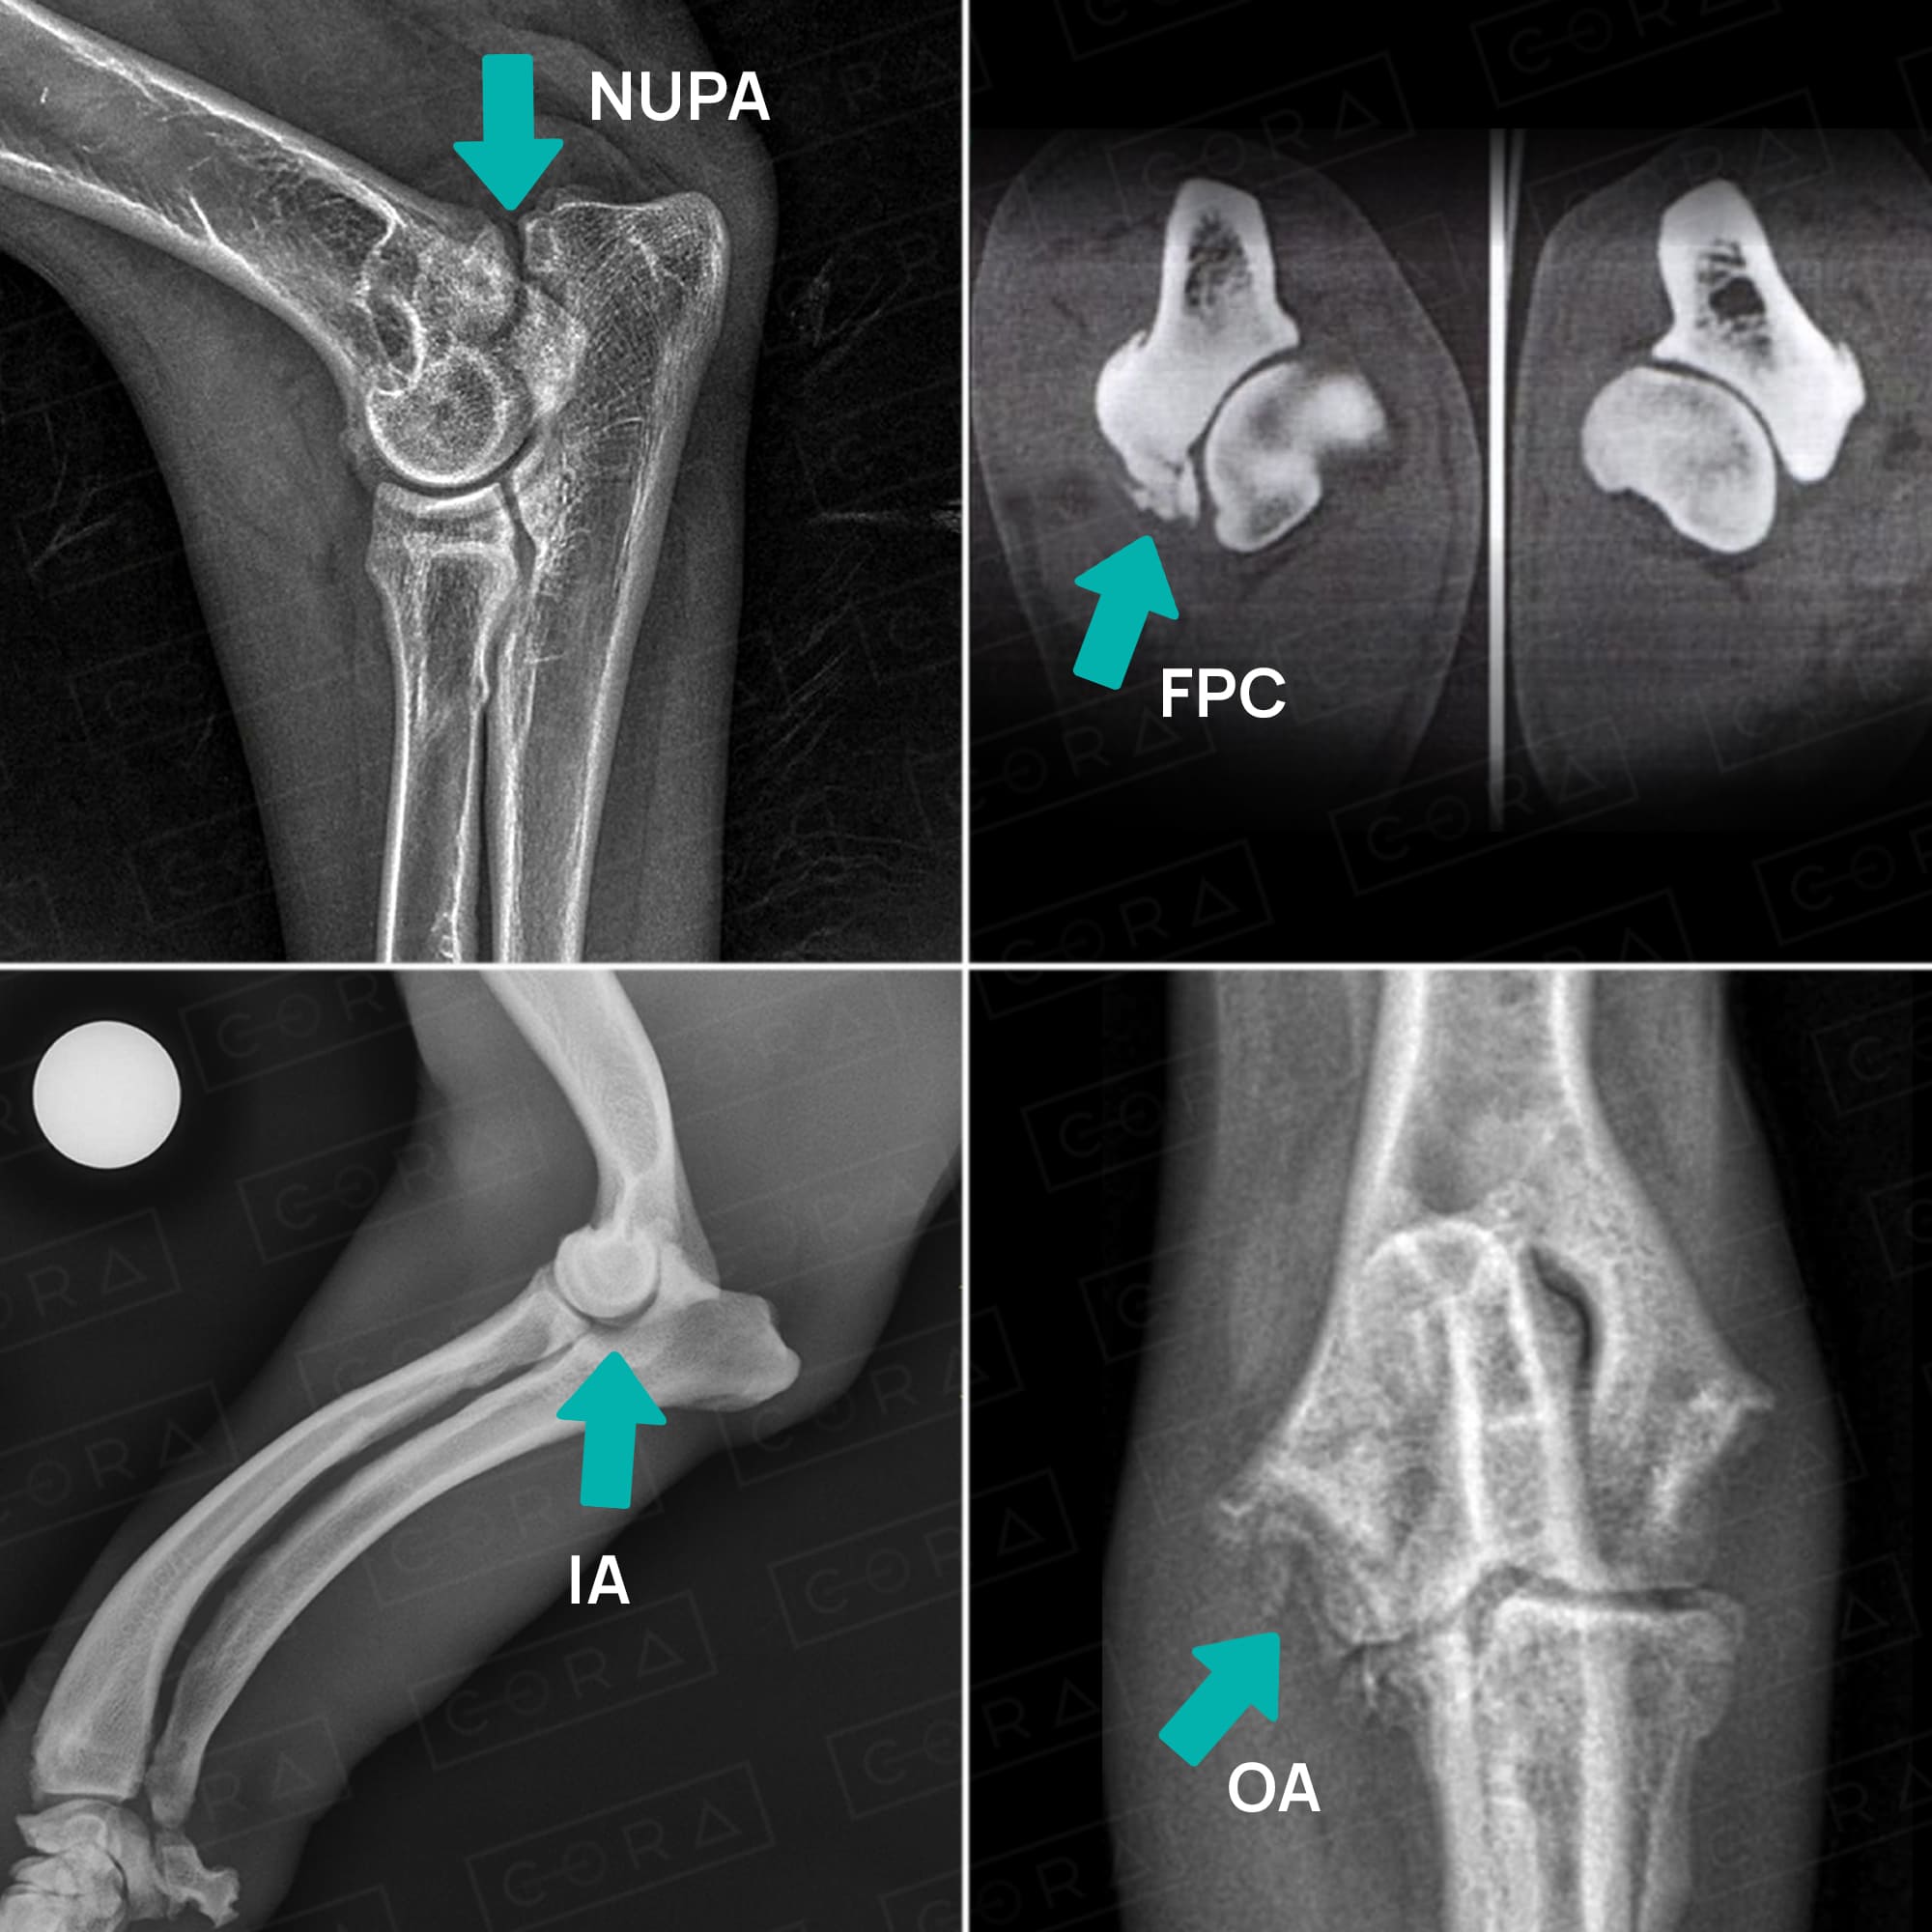

É um conjunto de doenças de caráter genético que podem acometer de forma simultânea ou isoladas a

articulação do cotovelo, entre elas:

- osteocondrose,

- não união do processo ancôneo,

- fragmentação do processo coróide medial,

- incongruência articular,

- levando, invariavelmente, a um quadro de osteoartrose.